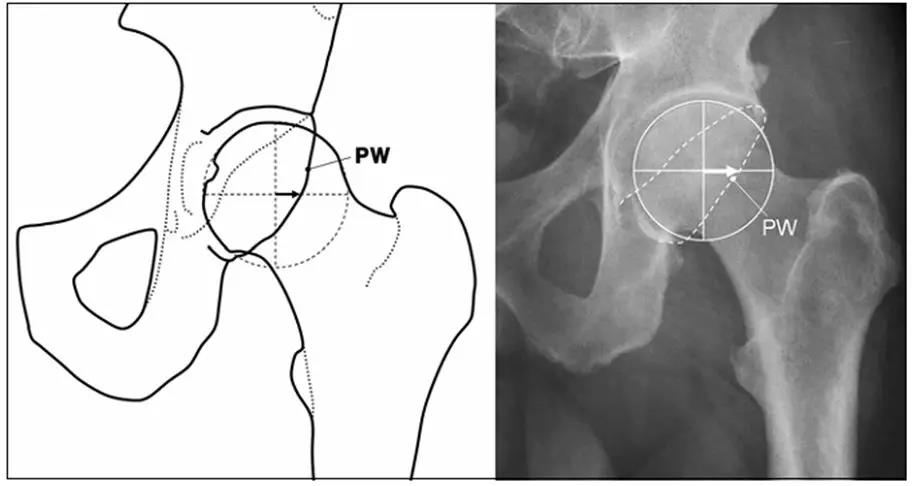

- IIL:髂坐线;AW:髋臼前壁缘;PW:髋臼后壁缘;A为股骨头被髋臼覆盖部分的宽度;E为股骨头未被髋臼覆盖部分的宽度;F为髋臼窝线。

髋臼过深,髋臼窝线位于髂坐线内侧。

- 髋臼窝线位于髂坐线内侧。

- LCE>39°时,提示髋臼过渡覆盖。

- 正常髋臼指数(AI)为正值,AI为0或负值提示髋臼过深。

- 髋臼过深:髋臼线位于髂坐线内侧。

- 髋臼突出:更内侧(成人:男性>3mm,女性>6mm;儿童:男性>1mm,女性>3mm。)

- 髋臼前突,股骨头与髂坐线相交